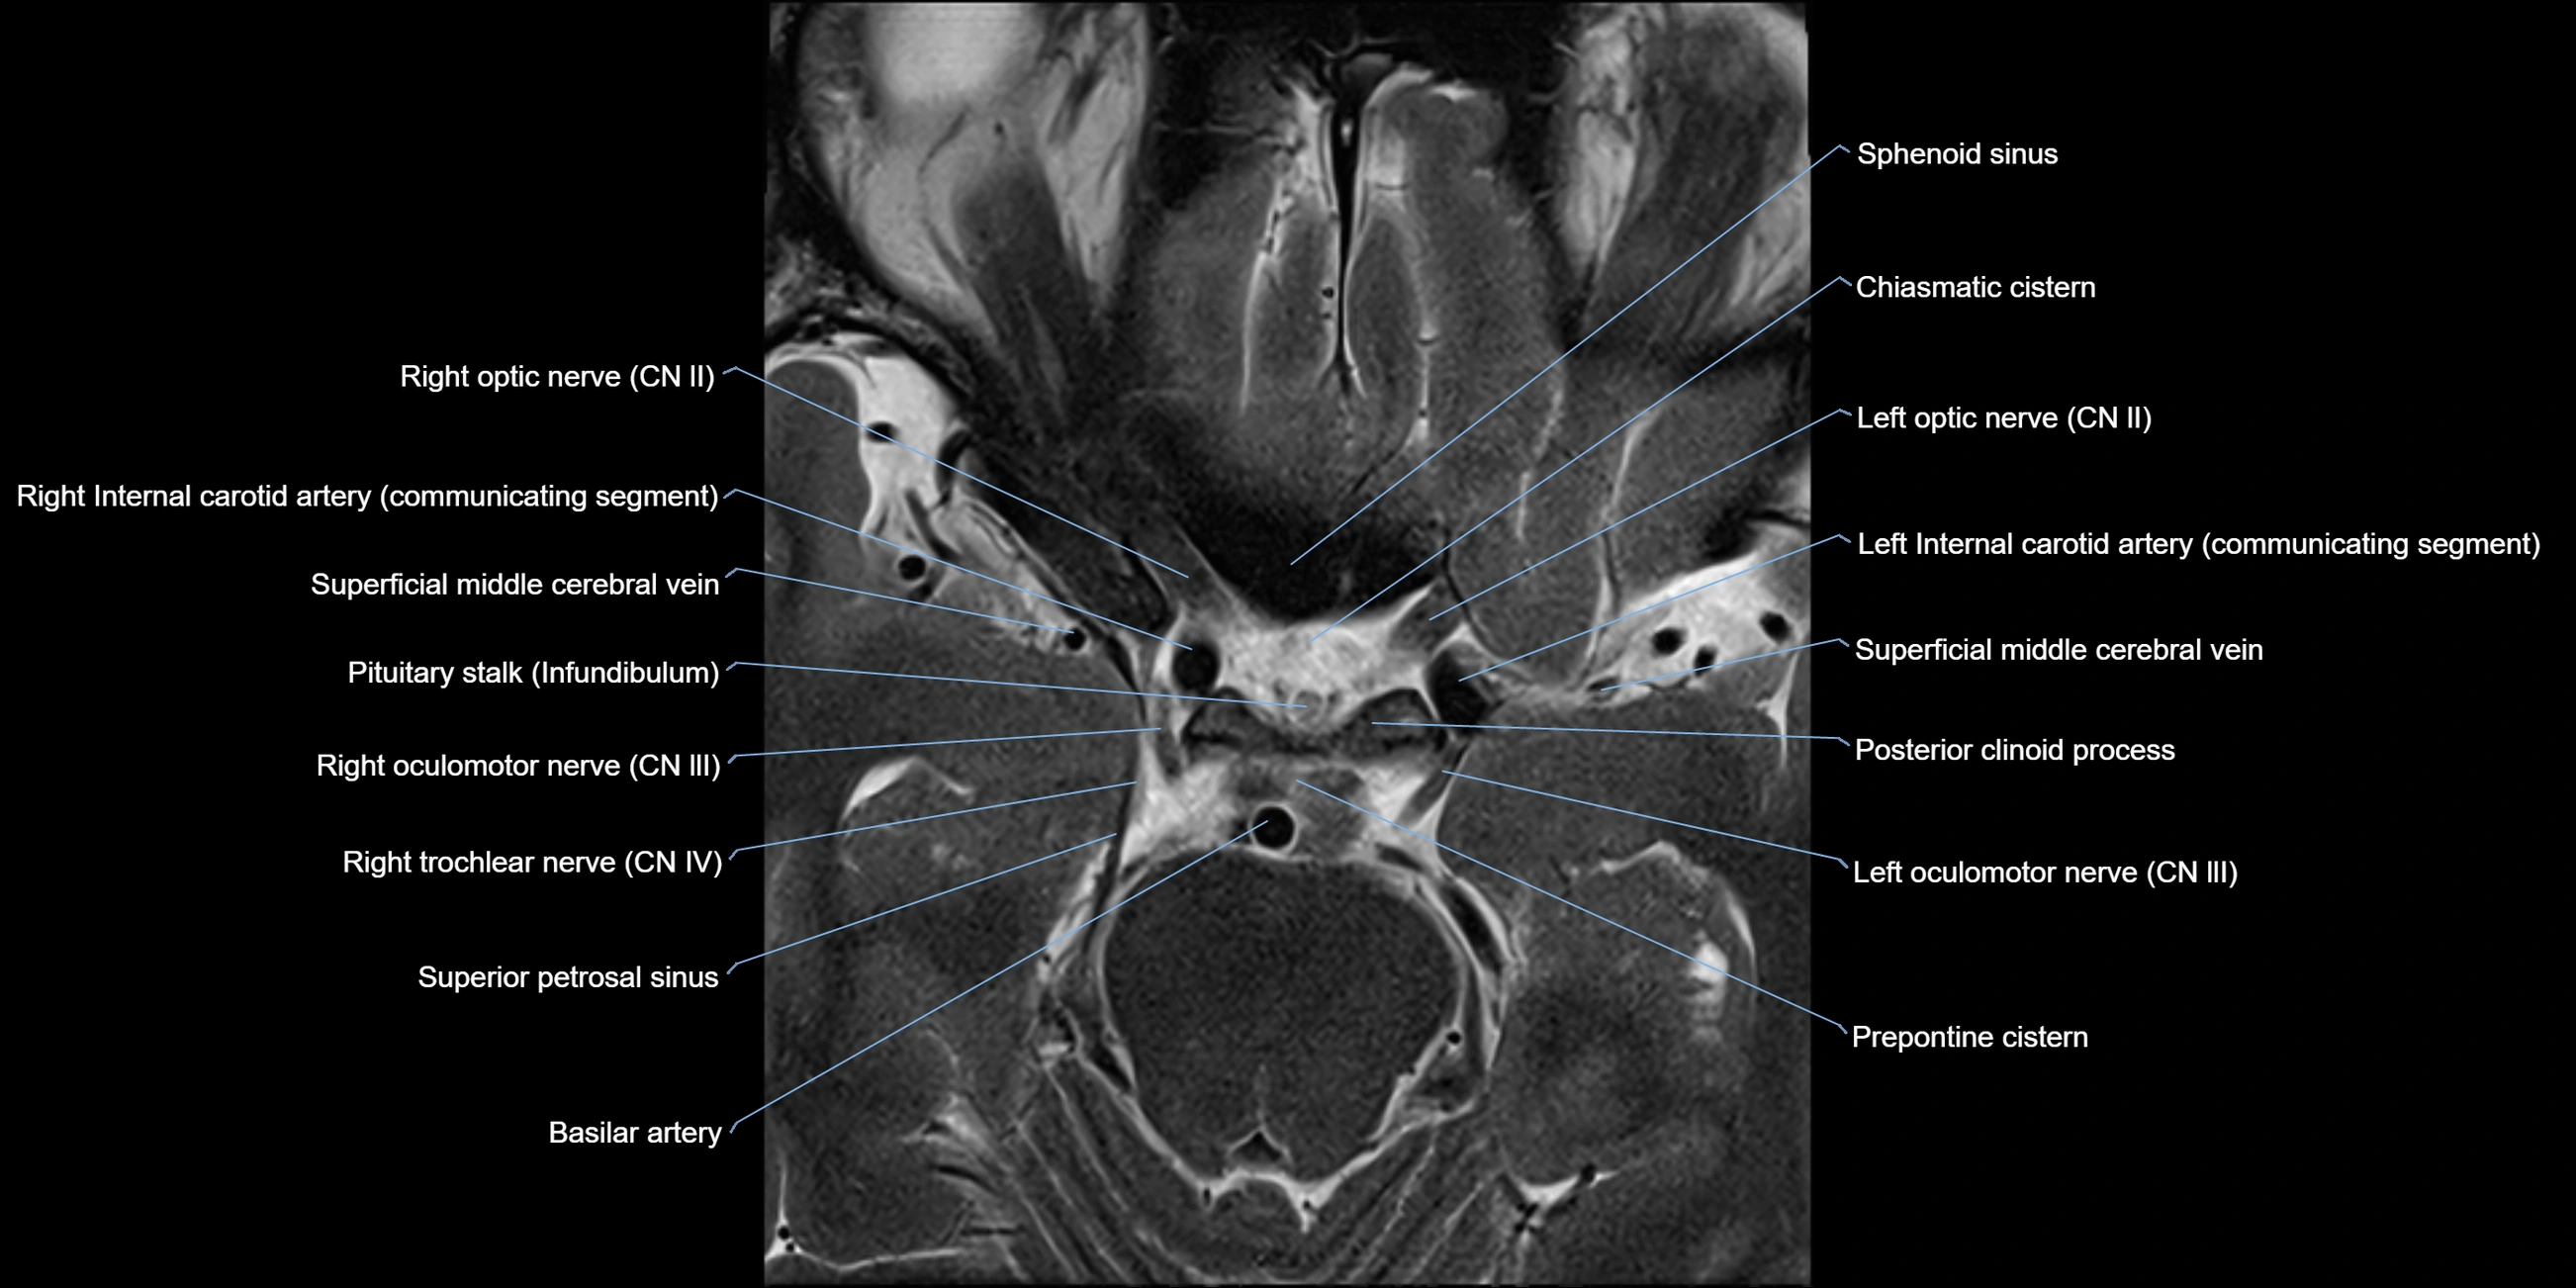

MRI Appearance

The abducens nerve is a small, thin, linear structure

Best visualized on high-resolution T2-weighted 3D MRI sequences (e.g., FIESTA or CISS)

Seen as a hypointense (dark) line running from the brainstem at the pontomedullary junction, traversing the prepontine cistern, and entering Dorello’s canal under the petrosphenoidal ligament, then into the cavernous sinus, and finally the orbit

May be challenging to visualize in standard MRI due to its small size

Pathology may be inferred by absence, displacement, or enhancement of the nerve